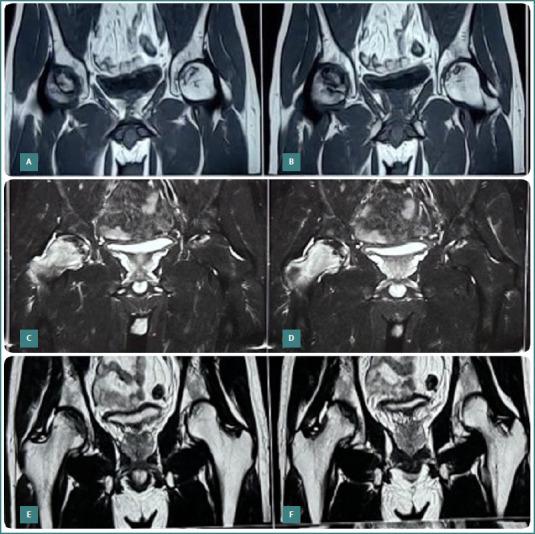

Osteonecrosis of the femoral head (ONFH) is a challenging condition that mainly affects young and middle-aged adults, causing pain, disability, and joint collapse. Current treatment options include medications, physical therapy, and surgical interventions such as core decompression and total hip replacement. However, there is growing interest in regenerative medicine for managing ONFH. This study evaluated the outcomes of core decompression augmented with adult autologous live cultured osteoblasts (AALCO) in patients with early-stage ONFH. Patients diagnosed with ONFH, Ficat-Arlet Grades 1, 2, and 3, underwent a staged procedure involving bone marrow aspiration and the cultivation of 48 million osteoblastic lineage cells. Subsequently, this culture was injected following core decompression and curettage of the necrotic area in the femoral heads. Patients were then followed for 18 to 26 months and evaluated for radiological progression of the disease and changes in functional outcome using the Harris Hip Score (HHS) and Visual Analog Scale (VAS). Forty-eight hips (34 patients with 14 bilateral ONFH) were included in the study and followed up for 18 to 26 months. During this period, 29 patients (40 hips) exhibited progressive signs of healing, resulting in a significant improvement in the mean HHS and a reduction in VAS scores. Core decompression augmented with implantation of autologous live cultured osteoblasts is a reliable treatment approach for managing the early stages of ONFH in young patients caused by various factors. The method aims to halt disease progression through osteoblastic stem cell-mediated new bone formation, leading to improved functional outcomes and potentially delaying or avoiding the need for total hip arthroplasty.

股骨头坏死(ONFH)是一种具有挑战性的病症,主要影响中青年,会导致疼痛、残疾和关节塌陷。目前的治疗选择包括药物治疗、物理治疗以及诸如髓芯减压和全髋关节置换等外科干预措施。然而,再生医学在治疗ONFH方面的关注度日益增加。本研究评估了在早期ONFH患者中采用成人自体活培养成骨细胞(AALCO)增强髓芯减压的效果。诊断为ONFH、Ficat-Arlet分级为1、2和3级的患者接受了分阶段手术,包括骨髓抽吸和培养4800万个成骨谱系细胞。随后,在股骨头坏死区域进行髓芯减压和刮除术后注入这种培养物。然后对患者进行18至26个月的随访,并使用Harris髋关节评分(HHS)和视觉模拟量表(VAS)评估疾病的放射学进展和功能结果的变化。该研究纳入了48个髋关节(34例患者,其中14例为双侧ONFH),并随访了18至26个月。在此期间,29例患者(40个髋关节)表现出愈合的进展迹象,导致平均HHS显著改善,VAS评分降低。自体活培养成骨细胞植入增强的髓芯减压是治疗由各种因素引起的年轻患者早期ONFH的可靠治疗方法。该方法旨在通过成骨干细胞介导的新骨形成来阻止疾病进展,从而改善功能结果,并有可能延迟或避免全髋关节置换的需要。